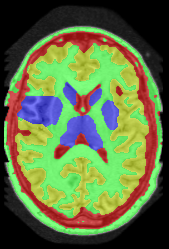

![]() |

||||

| (a) tree and min-margins | ||||

|

Subject 2 |

Subject 3 |

Subject 4 |

| ground truth | a-exp [7, 8] | QPBO [25, 8] | ours | |

Brain Segmentation:

We combined the labeled regions in dataset [19] (T1W MRI) to create the tree shown in Fig. 15(a). In this setting, the data term is the sum of color model penalty and an shape prior [5] based on an automatically extracted brain mask using [16],

| (5) |

where is the intensity at pixel and is the Euclidean Distance Transform of the extracted brain mask. Min-margins are shown in Fig. 15(a). We also added a Hedgehog prior [13] for the sub-cortical grey-matter to help our energy differentiate between grey-matter and sub-cortical grey-matter.

In this application our method outperformed QPBO in most cases and a-exp in all cases. In fact a-exp always converged to a weak local minima in this setting, see Fig. 15. Based on our experience the quality of a-exp result depends on various factors, e.g. tree complexity, the number of min-margins introduced, the order in which labels are expanded, and the initial solution. For the subjects that QPBO was able to find the global optimal Path-Moves either found the global optimal or a very close solution.